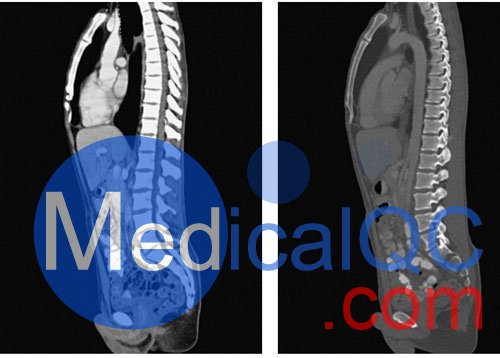

WEK57-01門靜脈期軀干模體,WEK57-01軀干模型模擬了門靜脈期的造影劑增強胸部、腹部和骨盆。它覆蓋了會陰的第二胸椎。

該模型可用于 CT(包括 CBCT)以評估和優化成像性能和后處理應用,包括支持 AI 的應用。它也適用于培訓目的。

該模型提供了對軟組織和骨組織的詳細而逼真的模擬。包括肺在內的空隙充滿了大約 -160HU的纖維素聚合物復合材料。

真實模擬脈管系統、骨骼和軟組織,包括肺、心臟、肝臟、膽囊、胰腺、脾臟、腎上腺、腎臟、胃、小腸、結腸、膀胱和前列腺。

右側髂外淋巴結腫塊。

WEK57-01門靜脈期軀干模體,WEK57-01軀干模型成像效果圖: